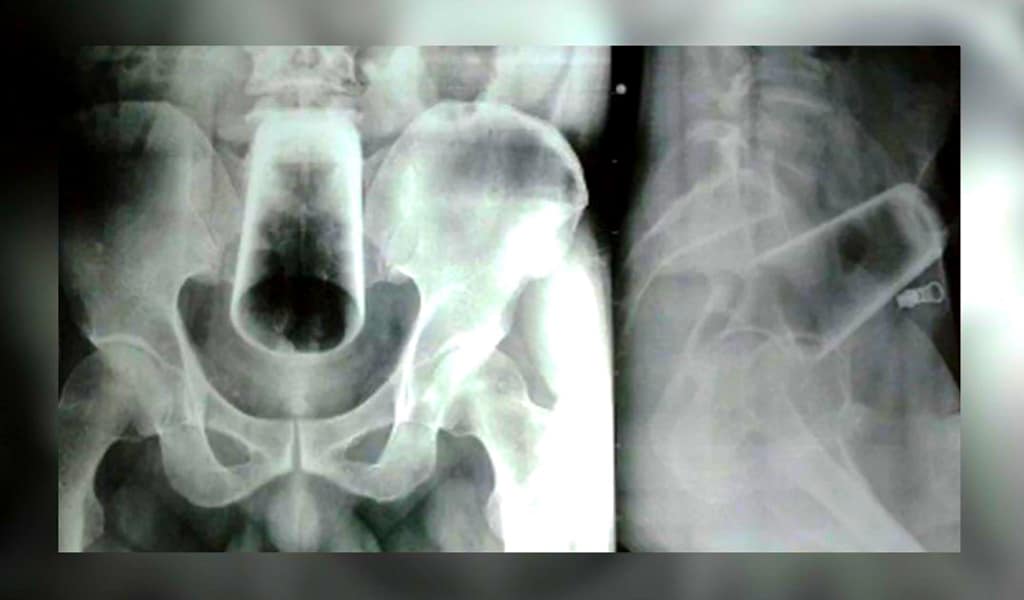

📌No entanto, ao chegar na unidade de atendimento, a equipe médica percebeu a gravidade da situação do paciente. Conforme identificado pela equipe do hospital, o copo acabou quebrando dentro do ân*s do homem, que não teve a identidade divulgada. Diante da gravidade do quadro, o paciente foi submetido a um procedimento cirúrgico para remoção do objeto e, até o momento, não há informações sobre o seu estado de saúde.